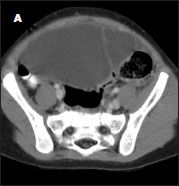

A CT scan with contrast showed a large (12 × 10 × 10-cm), septated, fluid-filled mass in the pelvis that compressed and displaced adjacent structures (A). A mesenteric or urachal cyst was suspected.